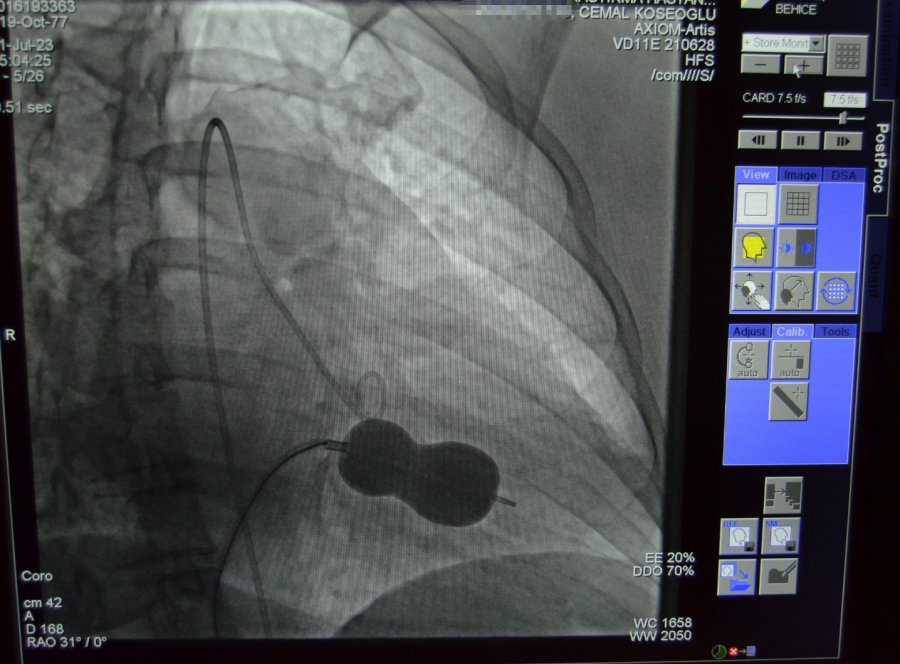

Alanya'da yaşayan 45 yaşındaki hasta Behice Kanmaz, nefes darlığı ve çarpıntı şikâyetleri ile Alanya Eğitim ve Araştırma Hastanesi'ne başvurdu. Hastanede detaylı yapılan ön tetkik ve değerlendirmeler neticesinde Kanmaz'da romatizmal mitral darlığı ve kalbin sağ tarafında büyüme tespit edildi. Romatizmal kalp hastalığına bağlı mitral kapakta gelişen darlık ve mitral kapakta büyüme nedeniyle kardiyoloji hekimleri hasta Behice Kanmaz'ın mitral darlığının ameliyatsız tedavisine karar verdi.

Yapılan işlem ile ilgili açıklama yapan ALKÜ Tıp Fakültesi Öğretim Üyesi Doç. Dr. Cemal Köseoğlu, "Hastanemizde ilk kez uygulanan bu işlemi kardiyoloji birimi hekimleri olarak birlikte değerlendirdik ve mitral balon yardımıyla işlemi yapma kararı aldık. Hastamız Behice Hanımı, Anjıyo ünitemizde hiç uyutmadan mitral balon yardımıyla ile kasıktan girerek daralmış kapağını bir buçuk saat süren işlem sonunda açtık. Son kontrollerimizi yaptık. Hastanın kalp kapağı gayet güzel çalışıyor. 2 gün yoğun bakımda takibi sonunda taburcu işlemlerini gerçekleştireceğiz" ifadelerini kullandı. Doç. Dr. Köseoğlu; tıp teknolojisindeki gelişmeler ve giderek artan ameliyatsız müdahale imkanları ile çok ciddi kapak müdahalelerini çok düşük risklerle yapabilme olanağı bulduklarını da sözlerine ekledi.